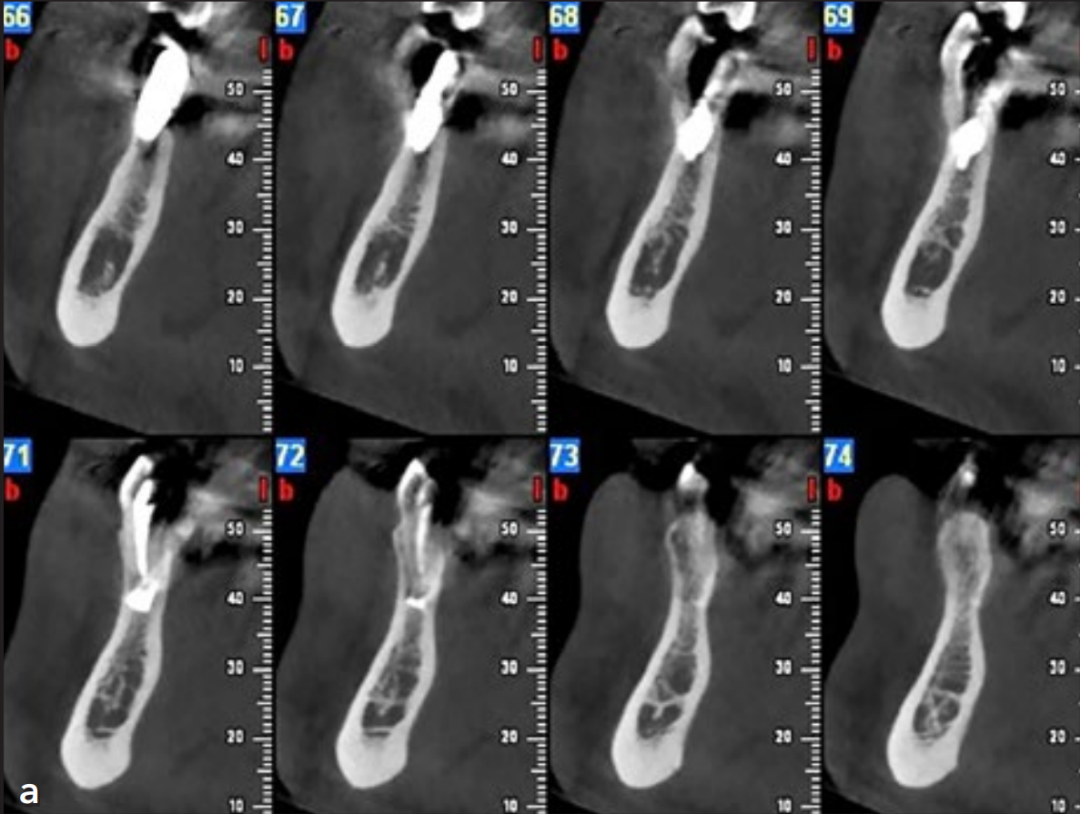

患者坚持双月维护计划,修复体功能良好,无主观不适主诉。术后4年行锥形束CT(CBCT)检查,影像学评估证实:

种植体周围骨结合状态稳定;

根尖区骨组织持续保持愈合状态;

未发现病理性改变(图4)

注意下颌右侧第一前磨牙的根尖神经横断。(a) 横断面图像。(b) 3D立体图。